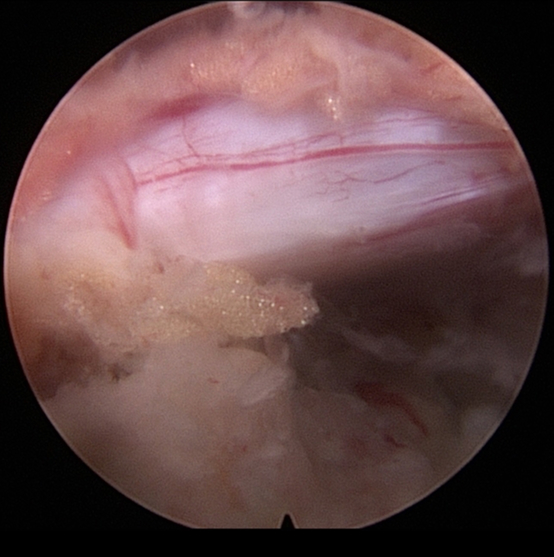

Πλάγια προσπέλαση

Πρόκειται για μια ακόμα πιο ειδική μέθοδο, κατά την οποία εισερχόμαστε μέσω του μεσοσπονδύλιου τρήματος και αποκτούμε πρόσβαση κατευθείαν στην δισκοκήλη χωρίς να χρειάζεται αφαίρεση οστικού τμήματος. Αποτελεί την λιγότερο επεμβατική μέθοδο όλων στην σπονδυλική στήλη, αφού χρησιμοποιεί φυσικά τρήματα για την είσοδο στον σπονδ. σωλήνα.